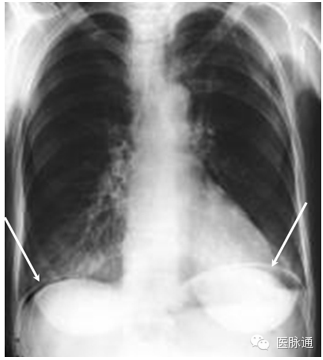

气腹指腹腔内气体,最常见于腹腔脏器穿孔。气体蓄积于腹腔的非重力依赖区。直立位胸片时,膈肌间的黑色的半月形(如图6箭头所示)的气体将分布于肝脏、脾脏和肠管。为保证气体充分移动,患者在拍片前应保持直立位至少5分钟。有时,X片中可见双壁或Rigler征,即肠壁内外气体形成的肠壁轮廓。

图6